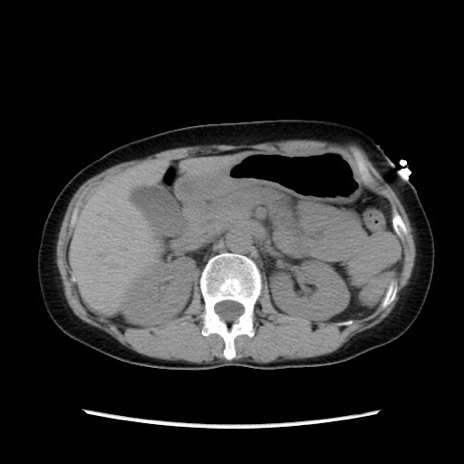

症例32(横断像)

【症例】40歳代 女性

【主訴】上腹部痛、嘔気・嘔吐

【現病歴】約9時間前頃から急に上腹部痛、嘔気、嘔吐が出現。改善しないため救急要請。

【既往歴】子宮頚癌(広汎子宮全摘術、放射線療法)、腸閉塞

【身体所見】腹部:平坦、軟、腸雑音亢進、上腹部を中心に腹部全体に圧痛あり。

【データ】WBC 8400、CRP 0.03